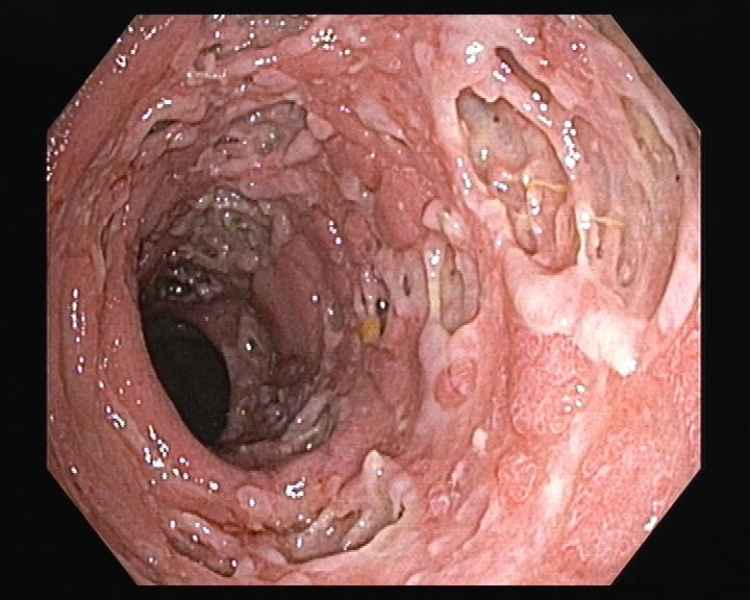

"A Nightmare on Elm Street"

Fotografias